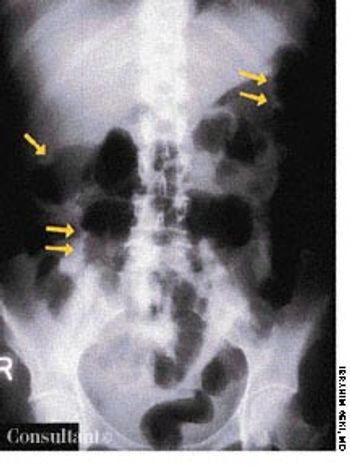

High-grade fever, chills, fatigue, malaise, and anorexia developed in a 35-year-old man following subclavian catheterization because of chronic renal failure of unknown cause. The patient, who had long-standing diabetes mellitus, was admitted to the ICU with the diagnosis of possible sepsis. The next day, he was found to have a grade 2/6 systolic murmur compatible with tricuspid regurgitation. This was confirmed when a 4-chamber echocardiogram (A) revealed a large single piece of vegetation (2 arrows) lying on the tricuspid valve, flapping in and out of the right ventricle. In a 2-dimensional echocardiogram of the right atrium and right ventricle (B), 3 arrows point to the vegetation. (RV, right ventricle; LV, left ventricle; RA, right atrium; LA, left atrium; TV, tricuspid valve.)